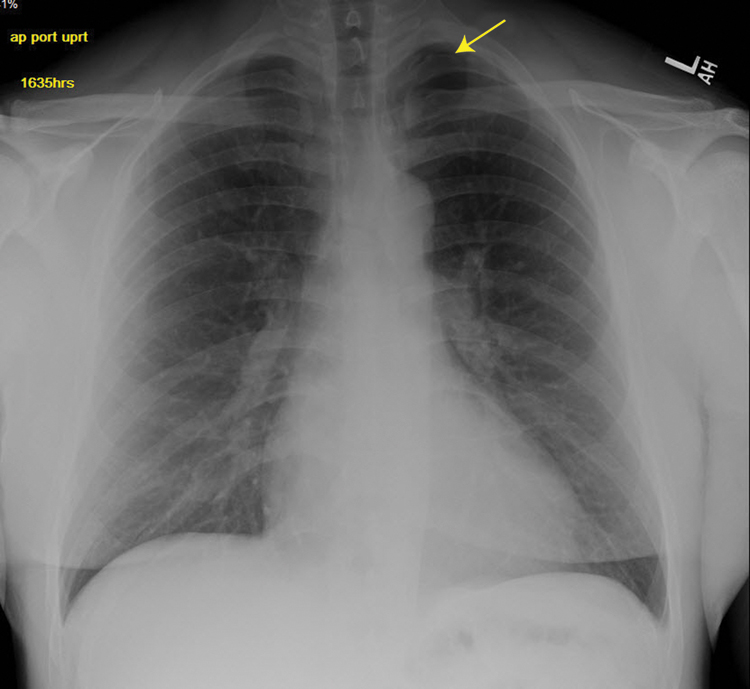

Initial evaluation in the emergency department included complete blood cell count and comprehensive metabolic panel, the results of which were unremarkable. Because of the dry cough, portable chest x-ray imaging was done. The radiograph raised concern for left apical pneumothorax (Figure 1). Subsequently, computed tomographic images of his chest without contrast revealed a small left apical pneumothorax (Figure 2).

Anterior-posterior upright chest radiograph demonstrating a small left apical pneumothorax in a 44-year-old man who had dry needling of the infraspinatus, supraspinatus, rhomboid, and paraspinal muscles.